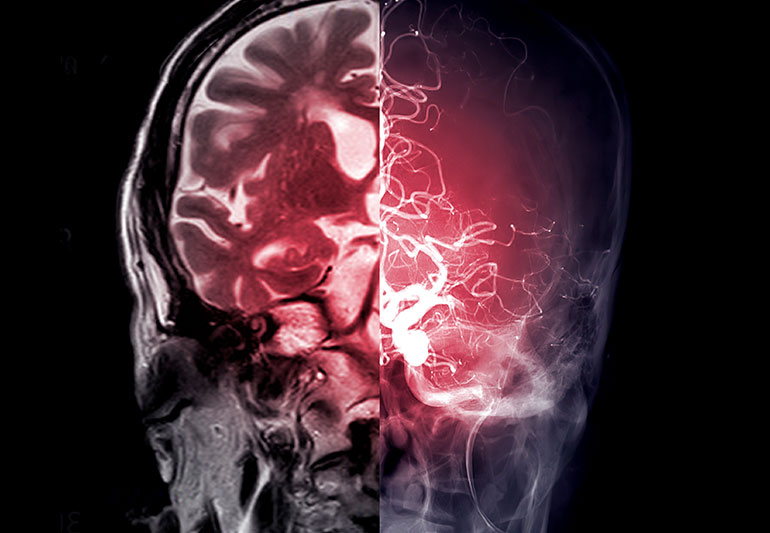

Khi ai đó bị đột quỵ, có nghĩa là một số phần mô não của họ đã chết. Đột quỵ thường là do dòng máu đến một phần não bị gián đoạn. Các vấn đề về mạch máu phổ biến có thể dẫn đến đột quỵ bao gồm cục máu đông hoặc các vấn đề liên quan đến mạch máu trong não, chẳng hạn như chứng phình động mạch hoặc viêm. Sau khi một người bị đột quỵ, bác sĩ sẽ cố gắng xác định nguyên nhân cụ thể, vì nguyên nhân cơ bản của đột quỵ thường quyết định liệu pháp tốt nhất. Tuy nhiên, có tới 40% trường hợp không thể xác định được nguyên nhân cụ thể gây ra đột quỵ. Một cơn đột quỵ mà nguyên nhân vẫn chưa được biết rõ sau khi đánh giá kỹ lưỡng được gọi là đột quỵ Cryptogenic, có nghĩa nguyên nhân là khó hiểu hoặc không rõ nguyên nhân. »»» Xem thêm: Đột quỵ động mạch não giữa: Nguyên nhân, triệu chứng và điều trị

Sau một cơn đột quỵ, đôi khi có thể khá khó khăn để xác định xem liệu việc cung cấp máu cho não bị gián đoạn là do cục máu đông hình thành tại chỗ (huyết khối), cục máu đông di chuyển đến não từ nơi khác (tắc mạch) hay một số vấn đề mạch máu khác. Một cơn đột quỵ không nên được gọi là do nguyên nhân gây bệnh cho đến khi đánh giá y tế đầy đủ không xác định được nguyên nhân cụ thể. Nói chung, việc đánh giá như vậy nên bao gồm chụp ảnh não (với chụp CT hoặc chụp MRI), chụp các mạch máu cung cấp cho não (nghiên cứu Doppler hai bên động mạch cảnh hoặc xuyên sọ), có thể chụp mạch và một số xét nghiệm trong phòng thí nghiệm để kiểm tra lượng đường trong máu, chức năng thận, chức năng tiểu cầu và chức năng đông máu (PT/PTT/INR). Ngoài ra, một nghiên cứu siêu âm tim đầy đủ về tim nên được thực hiện, tìm kiếm các nguồn tim tiềm ẩn gây tắc mạch. Các nguồn tim như vậy bao gồm các cục máu đông trong tim (thường là ở tâm nhĩ trái), bệnh lý màng phổi bằng sáng chế (PFO), chứng phình động mạch vách ngăn tâm nhĩ, rung nhĩ hoặc sa van hai lá (MVP). Nếu không xác định được nguyên nhân cụ thể gây ra đột quỵ ngay cả sau khi đã đánh giá kỹ lưỡng, thì đột quỵ được coi là do Cryptogenic. Có rất nhiều nguyên nhân tiềm ẩn gây ra đột quỵ do Cryptogenic và những người được đánh giá là bị đột quỵ do bệnh lý Cryptogenic là một nhóm không đồng nhất. Khi khoa học y tế đã phát triển thì khả năng xác định nguyên nhân của đột quỵ cũng được cải thiện, số lượng người được cho là bị đột quỵ do Cryptogenic đã bắt đầu giảm. Tuy nhiên, đột quỵ do Cryptogenic vẫn là một chẩn đoán khá phổ biến.